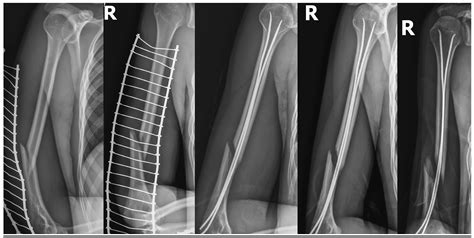

Diagnostic imaging plays a vital role in evaluating the radial groove of humerus and its associated structures. Radiographs, computed tomography (CT) scans, and magnetic resonance imaging (MRI) are commonly used to assess fractures, dislocations, and soft tissue injuries involving the humerus. These imaging modalities provide detailed views of the bone and surrounding tissues, helping clinicians identify any abnormalities or injuries in the radial groove of humerus area.

Radiographs are often the first-line imaging modality for evaluating humeral fractures. They provide a clear view of the bone structure and can help identify fractures, dislocations, and other bony abnormalities. CT scans offer more detailed images of the bone and can be used to assess the extent of fractures and the involvement of the radial groove of humerus. MRI, on the other hand, provides excellent soft tissue contrast and can help evaluate the radial nerve and other soft tissue structures in the area.